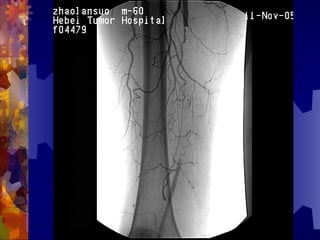

女 60 岁

 干性坏疽

干性坏疽

小趾坏疽